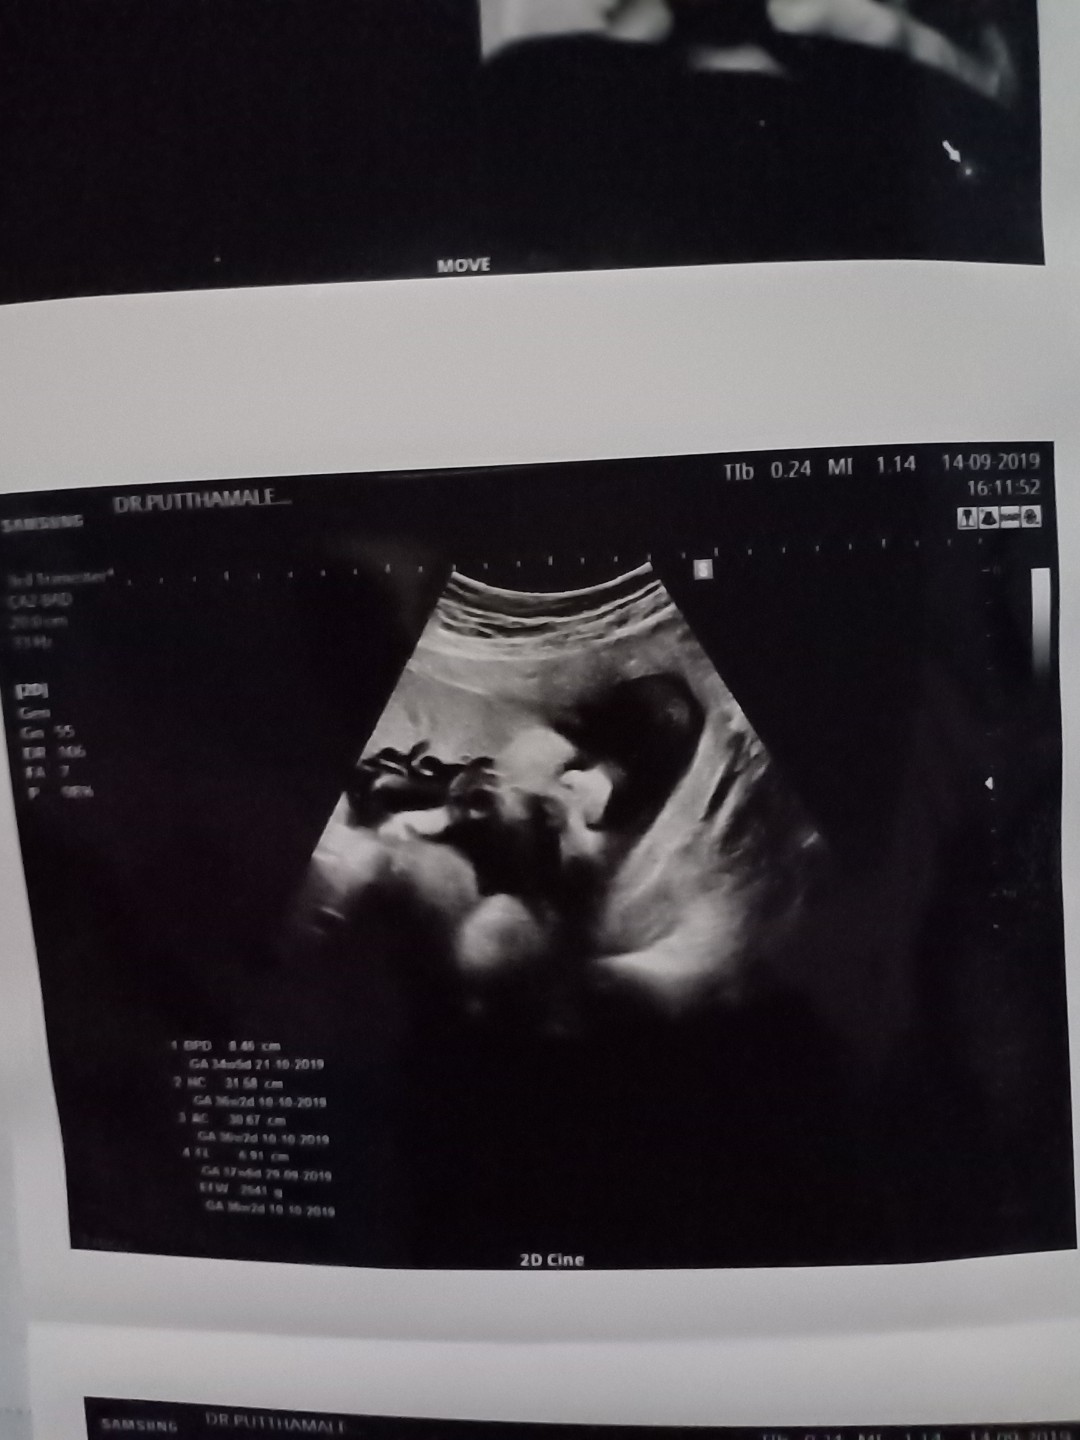

กำหนดคลอด 16 พ.ย เพศหญิง ตอนนี้ 34w+1 d นน.2,200จ้า ถอดแบบพ่อตั้งแต่ยุในท้องเลยจ้าา5555